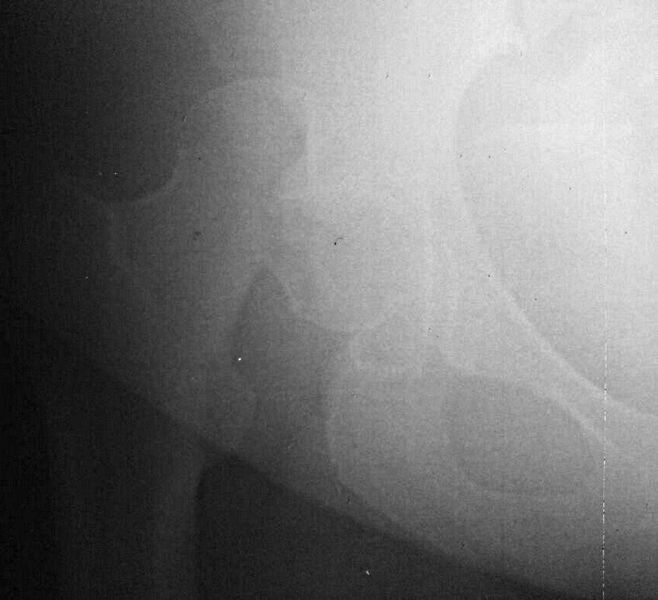

правой нижней конечности в день поступления. КТ контроль показал довольно

сносную картину результата репозиции. Отломок головки оставался в полости

сустава во время вывиха, т.к. видимо сохранилось прикрепление со связкой.

На КТ остается широкой суставная щель, что косвенно может указывать на

интерпозицию мягкими тканями, либо "встать на место" мешает медиальный

отломок головки.